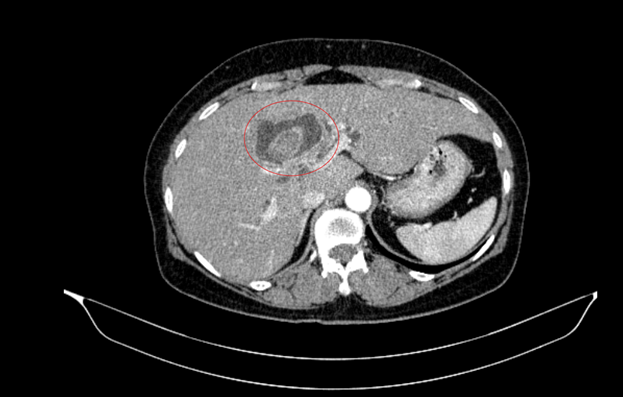

Hình ảnh sỏi đường mật tạo ổ áp xe gan - đường mật gan trái (vòng tròn màu đỏ). Giãn nhẹ đường mật trong gan hai bên. Dày thành nhẹ ngã ba đường mật trên phim chụp cắt lớp vi tính - Ảnh BVCC